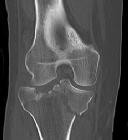

**CLINICAL SITUATION**

Figures 1 and 2 are the radiographs of a 35-year-old man who is brought into the emergency department after a motor vehicle collision. He is complaining of isolated knee pain. Examination reveals swelling, blood filled blisters, popliteal ecchymosis, joint line pain, and limited knee joint motion. His pulses and sensation are normal.

This knee injury is best described as a